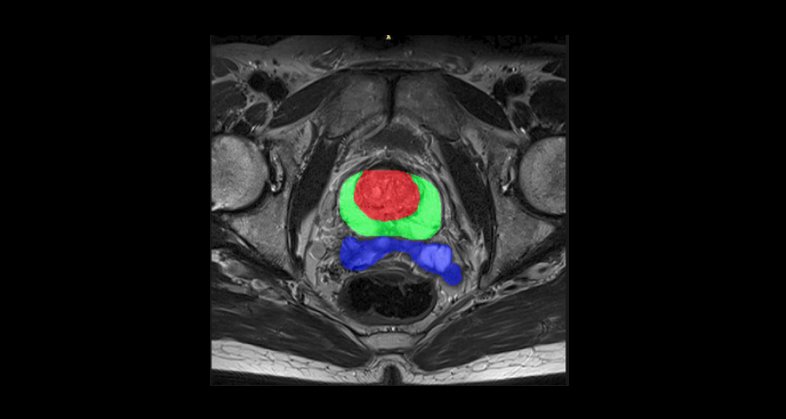

Our tissue-agnostic AI methods are applied at each stage of drug development programs. First we apply our AI techniques to harmonize image quality across hospitals and scanner models, then we perform automated organ and lesion detection. A tissue characterization follows to extract a signature based on the most relevant radiomics-based and deep features. These features are then used to develop predictive models of tumor growth, treatment response, overall survival, disease free survival, among many other patient outcomes.

Prediction of metastatic relapse in intermediate/high risk localized prostate cancer patients from staging medical images and clinical variables (PROVIDENCE study)